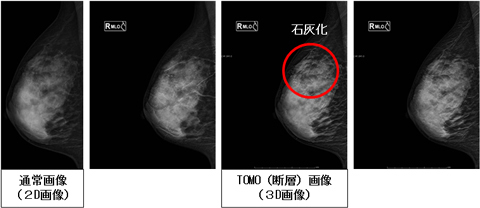

マンモグラフィとは、乳房のエックス線撮影のことをいいます。

マンモグラフィは、触診ではわからない乳がんの初期症状の一つである「小さな石灰化」を写しだすことが大きな特徴です。

新しい装置では最新機能である、乳房内部の構造を観察可能にする“トモシンセシス撮影”が可能となりました。

“トモシンセシス撮影”とは、エックス線管球を移動しながら連続的にエックス線を照射し、異なる照射角度から複数の画像を撮影して3Dデータとして再構成します。

通常のマンモグラフィ(2D画像)は、3次元の解剖学的情報を2次元で表示するため、乳線と病変が重なりあった画像となりますが、3D画像になることで病変位置を特定することが可能となる、最新機能です。